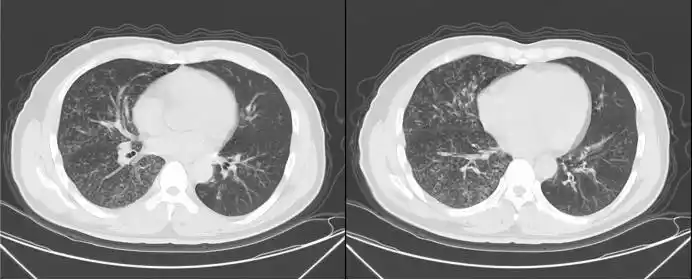

病例集锦Ⅱ 12 | 成人重症肺炎支原体肺炎-重症肺言